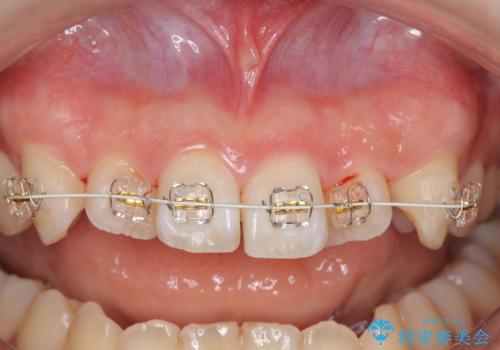

マウスピース矯正では改善の難しい前歯のねじれを前歯の部分ワイヤー矯正で改善したのち、インビザライン矯正を行い歯列を整えます。

インビザラインを行う前に前歯の部分矯正を行ったことで、しっかりとねじれが取れ整った歯列へと仕上げることが出来ました。